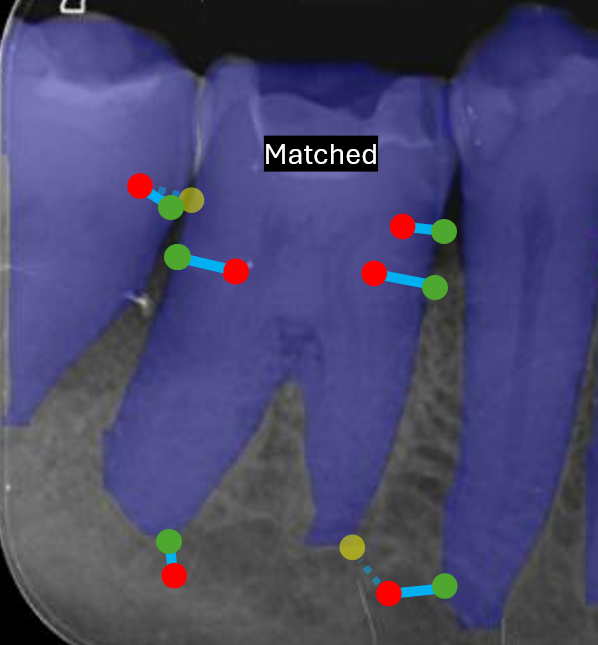

(e) Mask-Keypoint Matching

Refer to caption

(f) Mesial/Distal Determination

Figure 4: Handmade example diagrams, with synthetic data, depicting each stage of the post-processing module overlaid on Image104.

The post-processing module then determines the mask edge pixel associations for each predicted keypoint to the anatomical boundaries of each predicted tooth. The lowest Euclidean distance for a given keypoint to each closest edge pixel for all mask halves is chosen. This provides a geometric link between anatomical landmarks and boundary structures, allowing precise localisation relative to tooth edges. This step can be seen in Figure 4(d), where the red point is a single example of a predicted keypoint, the green point is the closest edge pixel for the closest segmentation mask halve, and yellow points are the closest edge pixel for all other mask halves.

To resolve which mask best corresponds to a given group of keypoints, the average distance between visible keypoints and their associated edges is computed. The mask with the smallest mean distance is selected as the most appropriate match, effectively filtering out false positive masks.

At this stage we have many keypoint-edge associations for all predicted keypoints, where each keypoint has an association for every predicted left and right side segmentation mask in the image. The post-processing module then proceeds to match each predicted keypoint group with its most likely associated predicted mask, by choosing the mask with the lowest average distance across all visible keypoints in the group. This process filters out false postive mask predictions, by disregarding non matched masks. This process can be seen in Figure 4(e), where green points are the closest edge pixel for a given predicted red keypoint, and yellow keypoints are the edge pixels for the matched segmentation mask if that keypoint’s closest edge pixel is not with the matched mask.

Finally, the post-processing module determines which sides of the image are mesial and distal. These are determined by distance based majority voting across visible keypoints for mesial and distal related keypoints. Each keypoint is assigned to the closest side of the matched mask, and votes are accumulated by anatomical keypoint class. The side with the most votes for mesial keypoints defines the mesial half, with the distal side assigned as its inverse. The final post-processed keypoints replace raw predictions when appropriate, ensuring consistent anatomical alignment across all teeth, as shown in Figure 4(f).